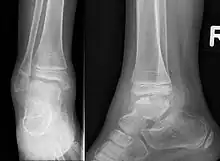

| Trevor disease in a nine-year-old girl: talus | |

This disorder is rare, and is characterised by an asymmetrical limb deformity due to localized overgrowth of cartilage, histologically resembling osteochondroma. It is believed to affect the limb bud in early fetal life. The condition occurs mostly in the ankle or knee region and it is always confined to a single limb. This usually involves only the lower extremities and on medial side of the epiphysis. It is named after researcher David Trevor.[1]

Trevor disease was first described by the French surgeon Albert Mouchet and J. Belot in 1926. In 1956, the name "dysplasia epiphysealis hemimelica" was proposed by Fairbank.[1] The usual symptoms are the appearance of an osseous protuberance, on one side of the knee, ankle or foot joint which gradually increases Radiologically,[14] the condition shows a nonuniformity of growth and multiple unconnected ossification centers around the epiphyses.[8]